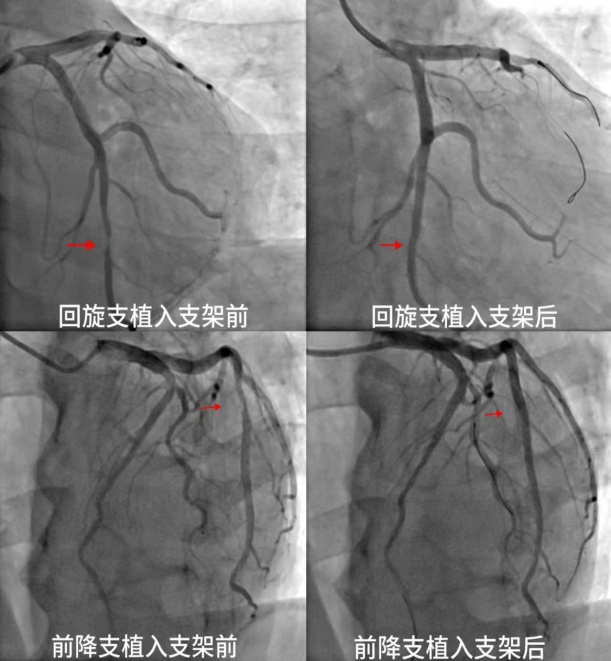

日前,患者王先生(化姓)因持续胸闷到十堰市人民医院就诊,该院心内科2病区主任吴三五博士带领团队经过精确诊断,迅速安排手术打通严重狭窄的心脏血管,帮助王先生恢复健康。根据王先生的病情,吴三五博士团队经心电图、心脏彩超等检…

近日,一面绣着“医术精湛品德优,服务热忱如亲人”的鲜红锦旗,在十堰市人民医院心内科2病区徐徐展开,见证了又一段技术与温度并重的健康故事。患者王先生(化名)因持续胸闷症状来到十堰市人民医院就诊。通过心电图、心脏彩超等一系列…